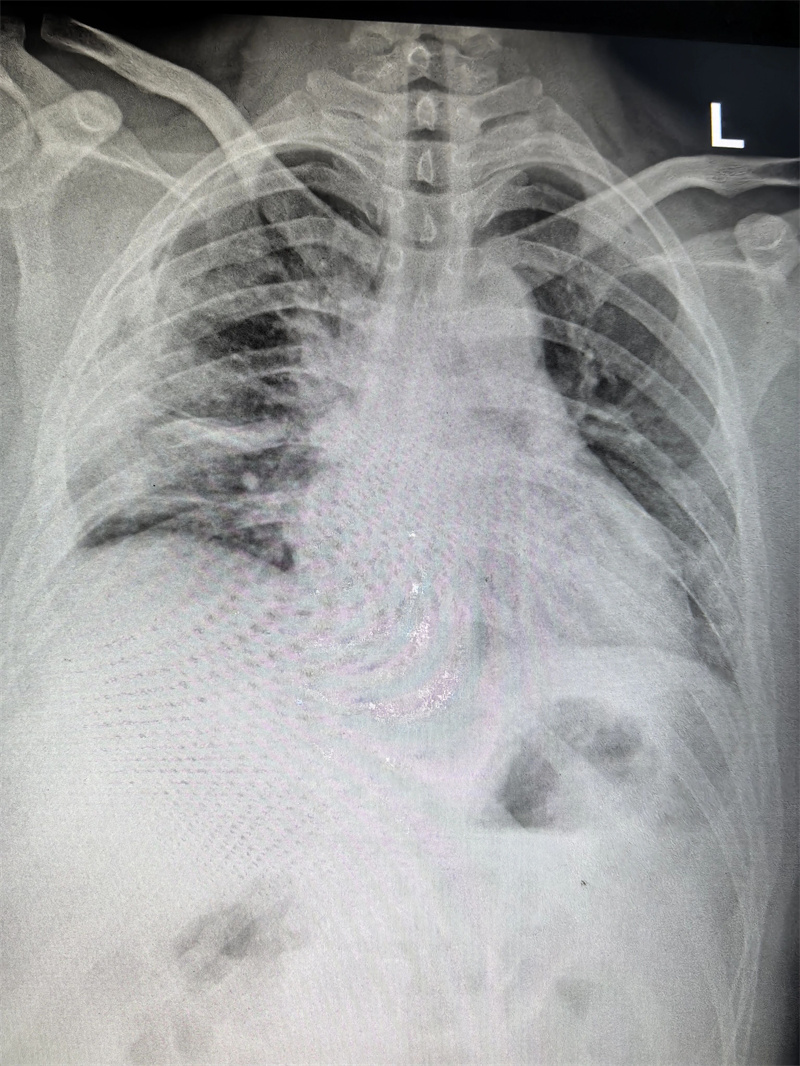

四个月前,23岁的小雨(化名)因胸闷前往医院就诊,CT检查结果显示右侧胸腔靠上位置出现包裹性脓胸,并进行穿刺检查,最终确诊为结核性包裹性脓胸,这个消息让小雨和家人陷入了深深的焦虑之中。

看着日益憔悴的小雨,医生建议手术治疗。术前,田子刚主任和宋巍峰医生在全面评估了小雨各项指标后,确定符合手术标准,便与麻醉科以及护理团队紧密配合,为小雨实施胸腔镜下胸膜剥脱术。